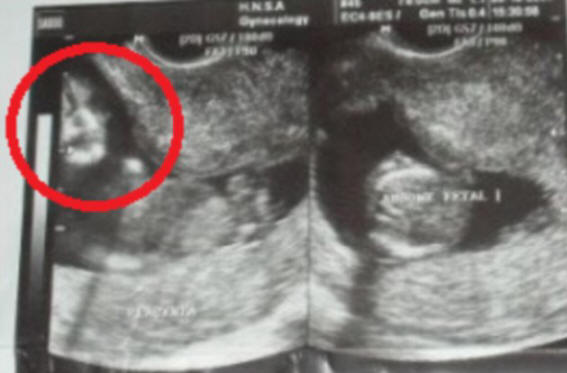

Házastársak Marcelo és Famela de Souza (Marcelo és Phamela de Souza) megdöbbent, amikor ultrahanggal látta születendő gyermekét a késő anya Marcelo arcához hasonló kép.

Az egyik képen hirtelen valahol furcsa “arc” jelent meg a méhből

Az eljárást a terhesség 10 hetében és a jövőbeli apán hajtottuk végre azonnal észrevette a képernyőn egy furcsa képet, de félni mondani erről a feleségének. De ő maga hamarosan látta az arcot a képen, és megmutatta a férjének. Marcelo szerint nagyon hasonlóan anyja arcához, aki mindössze 4 hónappal ezelőtt halt meg.